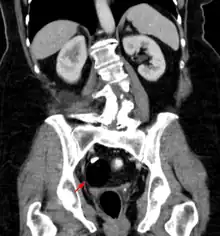

The most diagnosed fetal teratomas are sacrococcygeal teratoma (Altman types I, II, and III) and cervical (neck) teratoma. Because these teratomas project from the fetal body into the surrounding amniotic fluid, they can be seen during routine prenatal ultrasound exams. Teratomas within the fetal body are less easily seen with ultrasound; for these, MRI of the pregnant uterus is more informative.[26][27]

Diagnosis

Teratomas are thought to originate in utero, so can be considered congenital tumors. Many teratomas are not diagnosed until much later in childhood or in adulthood. Large tumors are more likely to be diagnosed early on. Sacrococcygeal and cervical teratomas are often detected by prenatal ultrasound. Additional diagnostic methods may include prenatal magnetic resonance imaging. In rare circumstances, the tumor is so large that the fetus may be damaged or die. In the case of large sacrococcygeal teratomas, a significant portion of the fetus' blood flow is redirected toward the teratoma (a phenomenon called steal syndrome), causing heart failure, or hydrops, of the fetus. In certain cases, fetal surgery may be indicated.